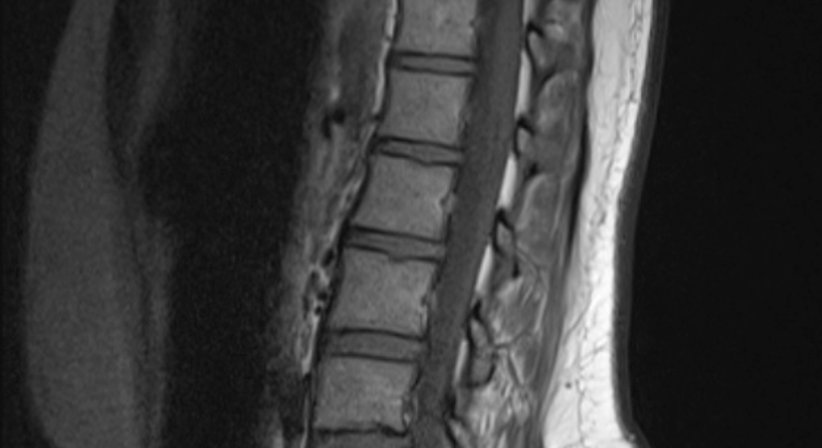

Die Magnetresonanztomographie funktioniert auf der Basis von elektromagnetischen Impulsen (ähnlich den herkömmlichen Radiowellen). Durch diese werden im Körper befindliche Wasserstoffkerne, die in den verschiedenen Geweben unterschiedlich dicht anzutreffen sind, zu einer kurzen Bewegung angeregt, die dann wiederum mittels sehr sensibler Sensoren gemessen werden kann. Die gesammelten Daten werden mittels Computer in Schnittbilder umgerechnet.

Die hohen Kosten der Untersuchung wird durch eine herausragende Bildqualität und einen hohen diagnostischen Wert gerechtfertigt. Durch die Verabreichung von speziellem Kontrastmittel kann die Aussagekraft der Untersuchung noch gesteigert werden. Besonders im neurologischen Bereich, also zur Beurteilung des Gehirnes, ist diese Methode unübertroffen, im Brustraum aber liefert beispielsweise die CT mehr Information.